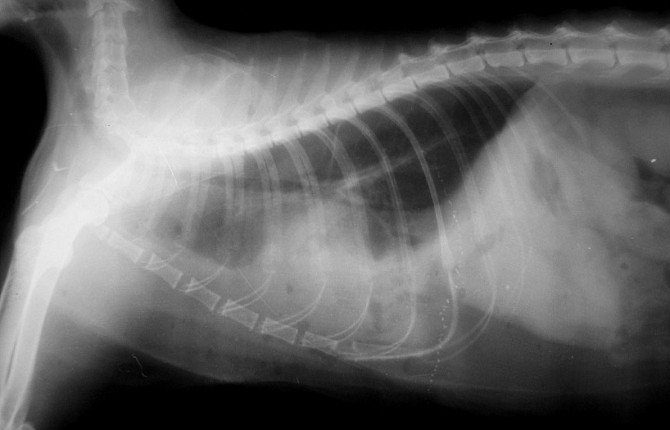

2. рентгенография грудной клетки – данный вид исследования позволяет определить наличие плеврального выпота, пневмоторакса, гидроторакса.

Пневмоторакс – это скопление свободного воздуха в плевральной полости.

Дренажную трубку удаляют при восстановлении дыхания, рентгенографическом подтверждении расправления легких, достижении объема дренируемой жидкости менее 5 мл/кг/сутки, а также при отсутствии утечки воздуха в дренажной системе.

Удаляют дренаж под местной анестезией и накладывают тугую повязку. В течение следующих суток животное остается под тщательным наблюдением ветеринарных врачей для мониторинга признаков рецидива. На следующий день после снятия дренажа проводится контрольное рентгенографическое исследование. При положительной динамике животное на поддерживающей терапии выписывают домой с назначением контрольных наблюдений и диагностических мероприятий.